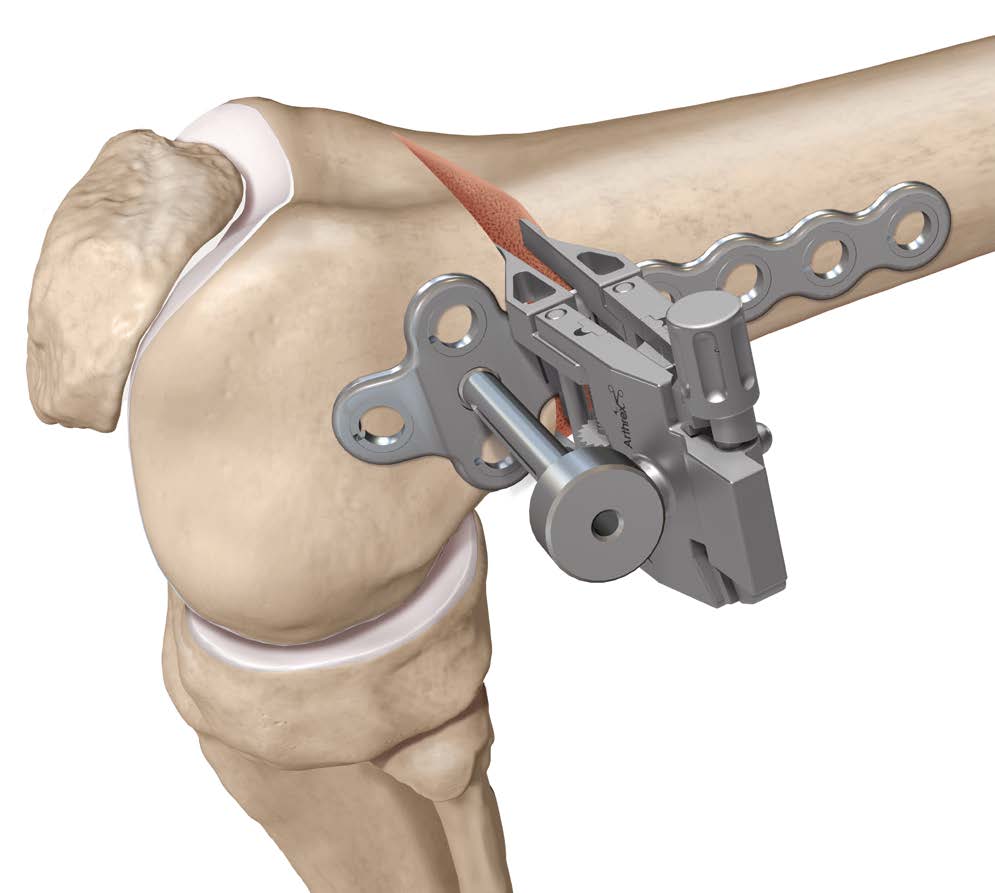

Technique

Arthrex ContourLock Distal Femoral Osteotomy Plates

Patient supine on a radiolucent table

Surgical approach

- lateral 12 - 15 cm incision

- split iliotibial band

- ligate perforators and elevate vastus lateralis off intermuscular septum anteriorly

- release intermuscular septum posteriorly at metaphyseal-diaphyseal junction

- protect neurovascular bundle

Osteotomy

- insert guide wires

- proximal lateral to distal medial

- proximal 1 - 2 cm above flare of lateral condyle

- aim towards adductor tubercle

- risk of medial hinge fracture reduced if osteotomy at or distal to adductor tubercle

- ensure these are perpendicular to the femoral shaft in the sagittal plane

- above patellofemoral joint and posterior condyles

- stop osteotomy 1 cm short of medial cortex

Open osteotomy

- maintain medial cortical hinge

- limit opening wedge to reduce fracture risk

Distal femoral locking plate + bone graft